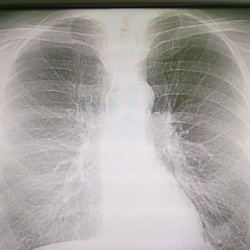

Добрый день. Подскажите пожалуйтса как описать в нижних отделах левого легкого.. как образование слева ?